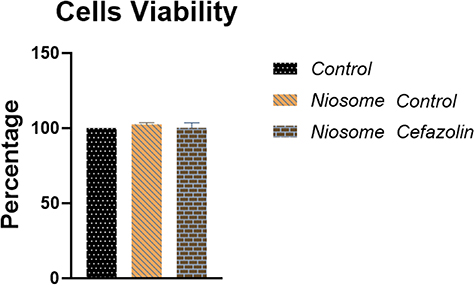

2.4.4. Cell viability

Cell viability was measured with 3-(4,5-dimethylthiazol-2-yl)-2,5-diphenyl tetrazolium bromide (MTT) (Sigma, USA) using a colorimetric assay [30, 31]. Five thousand normal human fibroblasts were seeded in 100 μl of culture medium per well in 96-well plates and incubated for 24 h at 37 °C. Different concentrations of niosomes were added to the cells in triplicate and DMSO was used as the negative control. After 24 h incubation, the treated cells were washed by PBS (5 mgml−1). Two hundred microliters of MTT-contained culture medium with the final concentration of 500 μg ml−1 was added and incubated for 3 h at 37 °C. The culture medium was discarded and 100 μl of DMSO (Sigma, USA) was added. After 30 min incubation, the final absorbance was read at 570 nm with Epoch microplate spectrophotometer (USA). The cell viability percentage was calculated by the following formula (all experiments were performed in triplicate):

3.4. Niosomes cytotoxicity

The results showed that cefazolin-loaded niosomes did not have cytotoxic effects on the host cells in 24 h, 48 h, and 72 h post-exposure. The mean value of viable cells in loaded and non-loaded niosomes was determined approximately 100% and equaled to the control group (figure 5).

Figure 5. Comparison of cell viability of cefazolin-loaded, non-loaded niosomes and control using MTT colorimetric assay. Viability percentage in both treated and control groups was determined approximately 100 (P-value < 0.0001).